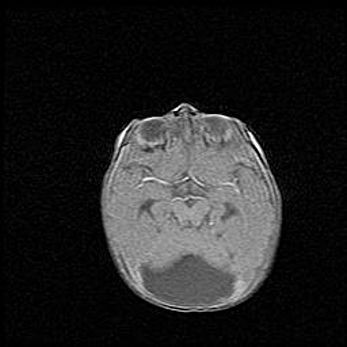

Сообщающаяся гидроцефалия. Кистозная энцефаломаляция головного мозга.

Возраст: 3 месяца 4 дня

Вес: 3100 г

Пол: женский

Окружность головы: 34 см

Срок гестации: 31 неделя

Кистозная энцефаломаляция головного мозга - одна из форм поражения головного мозга в детском возрасте. Характеризуется возникновением множественных и распространённых кист в коре, белом веществе и подкорковых образованиях головного мозга у плодов, новорождённых и детей раннего возраста. Развитие кистозной энцефаломаляции связано с внутриутробной асфиксией и гипотонией, родовой травмой, тромбозом синусов, пороками развития сосудов, инфекциями, сепсисом и другими причинами. Наиболее значимые инфекционные агенты: вирусы простого герпеса, цитомегалии, краснухи, токсоплазмы, энтеробактерии, золотистый стафилококк и другие.